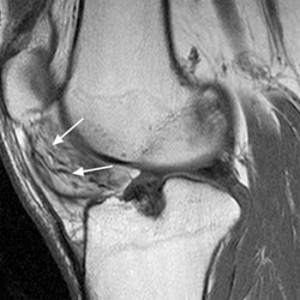

Аневризма под коленом

Аневризма под коленом 109 фотографий